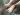

Çocuklarda topuk ağrısı, büyüme çağında sık görülen ortopedik rahatsızlıklardan biridir ve genellikle aktif, sporla ilgilenen çocuklarda ortaya çıkar. Topuk bölgesinde hissedilen bu ağrı, çoğu zaman yürüme, koşma veya zıplama sırasında belirginleşir. Büyüme döneminde topuk kemiğinin gelişimi devam ettiği için, bu bölgedeki kıkırdak dokular kolayca zorlanabilir. En yaygın nedenlerden biri sever hastalığı olarak adlandırılan topuk kemiği büyüme plağı iltihabıdır. Uygun tanı ve tedavi yöntemleriyle ağrı kontrol altına alınabilir ve çocukların günlük aktivitelerine rahatça devam etmesi sağlanabilir.

Çocuklarda Topuk Ağrısı, özellikle 8 ila 14 yaş arasındaki aktif çocuklarda sıkça karşılaşılan bir durumdur. Bu yaş aralığı, kemik gelişiminin hızla devam ettiği dönem olduğundan, topuk bölgesindeki büyüme kıkırdağı hassas hale gelir. Bu ağrı genellikle topuğun arka kısmında, aşil tendonu ile topuk kemiğinin birleştiği noktada hissedilir.

Topuk ağrısı bazen çocuğun yürümesini, koşmasını veya spor yapmasını zorlaştırabilir. Özellikle futbol, basketbol, jimnastik veya koşu gibi zıplama ve ani hareketlerin yoğun olduğu sporlara katılan çocuklarda bu rahatsızlık daha sık görülür. En yaygın nedenlerden biri ise sever hastalığı olarak bilinen topuk kemiği büyüme plağı iltihabıdır.